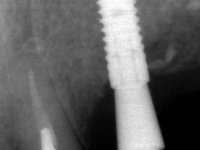

66-year-old male patient, non-smoker. It featured a 5-member metal-ceramic bridge with extreme mobility. Teeth 11 and 21 had infiltrated cervical margins. Both arches showed root exposure with signs of cervical abrasion. Composite resin “slots” were visible on the buccal surfaces of some mandibular teeth compatible with an orthodontic treatment with aligners that the patient was undergoing. After the imaging examination, it was found that the bridge's distal support, tooth 24, was irretrievably lost. The mesial pillars 11 and 21 had endodontic treatment and intraradicular posts. Teeth 25 and 26 also had endodontic treatment and extensive restorations in composite resin. In the lower jaw, two bridges were visible. In the third quadrant a 4-element bridge supported on tooth 35 and on 2 implants placed in the location of teeth 36 and 37. In the fourth quadrant a 3-element bridge supported on tooth 45 and an implant placed in the location of tooth 46. The patient presented a thick gingival phenotype and very good oral hygiene.

The patient was proposed to undergo a fixed oral rehabilitation consisting of a 2-element bridge over teeth 11 and 21 and a 5-element bridge over 3 implants that would be placed in the location of teeth 22, 24 and 26. The prosthetic structures would have an infrastructure in Zr coated with ceramic and the bridge over the implants would be screwed. The indicated extraction of teeth 25 and 26 and placement of an implant in the 26 site would imply surgery to fill the maxillary sinus. As the patient showed interest in having fixed temporary rehabilitation during treatment, we divided the treatment into 6 phases to achieve this goal: 1- Placement of a temporary bridge over teeth 11,21,25 and 26. With tooth extraction 24. 2- Placement of 2 implants in the location of teeth 22 and 24. 3- Placement of a temporary 6-element bridge over teeth 11 and 21 and over the implants. 4- Carrying out surgery to fill the maxillary sinus. 5 – Placement of the implant in the location of tooth 26 and in the area where the filling of the maxillary sinus was made. 6 – Placement of the definitive work.

A temporary acrylic bridge made in the laboratory with 7 elements was made, with teeth 11,21, 25 and 26 as pillars. The old bridge was removed and tooth 24 was extracted. The provisional bridge after relining was cemented in the mouth. Two implants were placed in the teeth 22 and 24 and 3 months after this intervention an impression was made to make a temporary bridge screwed over the implants and cemented to the teeth. The bridge was placed in the mouth and teeth 25 and 26 were extracted. 3 months later, surgery was performed to fill the maxillary sinus and 6 months later the implant was placed in the location of tooth 26. After osseointegration of this implant, the final impression was made for the final work. The bridge over the implants was permanently screwed on and the bridge over the teeth was cemented with resin-reinforced glass ionomer cement.